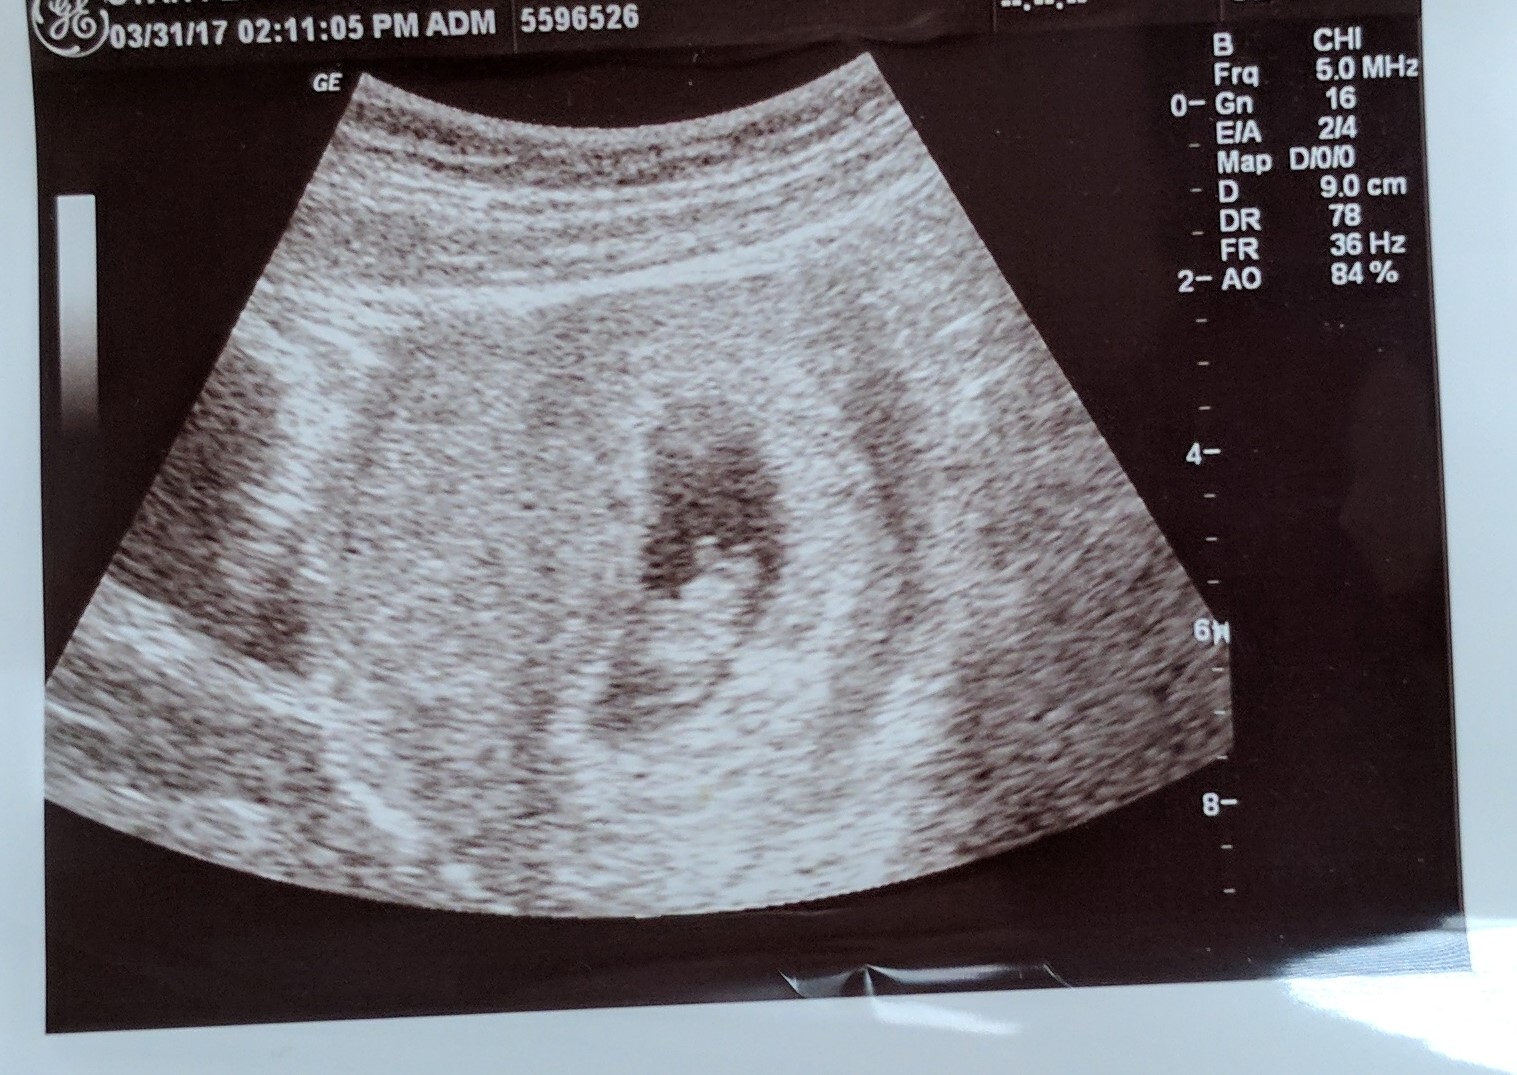

Had second u/s and again requested Abdominal--at 8weeks 5 days and I was even more anxious for this one. Like to the point I couldn't stop crying all morning. It was bad and I wasn't sure I wanted to know. But again all was well baby was measuring 8weeks 2 days and heart rate was 168. I cried when I heard that glorious heartbeat. We got to even see a little baby movement. Such a cute little gummy bear. They gave me list of meds that are safe during pregnancy and my records to take to my OB doctor. I can't believe I made it to actually graduate from the infertility clinic! I waited to schedule my first OB appt until after this u/s because every time in previous FET I had scheduled it I had to call and cancel due to miscarrying.

I had my first OB appointment on Thursday 4/6 and can I just say Dr. Nick Denson is wonderful! They did a quick u/s to reassure us and we saw the heart beating away and then we discussed a plan. He told me he'd be happy to see me every 1-2 weeks to ease my worry through first trimester due to my long history of trying and losses. He said we'd probably do a cervical cerclage (stitch) around 14-16 weeks and stay on progesterone through pregnancy as a preventative pre-term labor measure. He also referred me to Dr. Spencer a perinatal doctor that comes to IF occasionally (who happens to be Dr. Conway's my IVF doctors husband) to see if he has any other ideas or advice on when best placement time for cervix stitch would be etc.